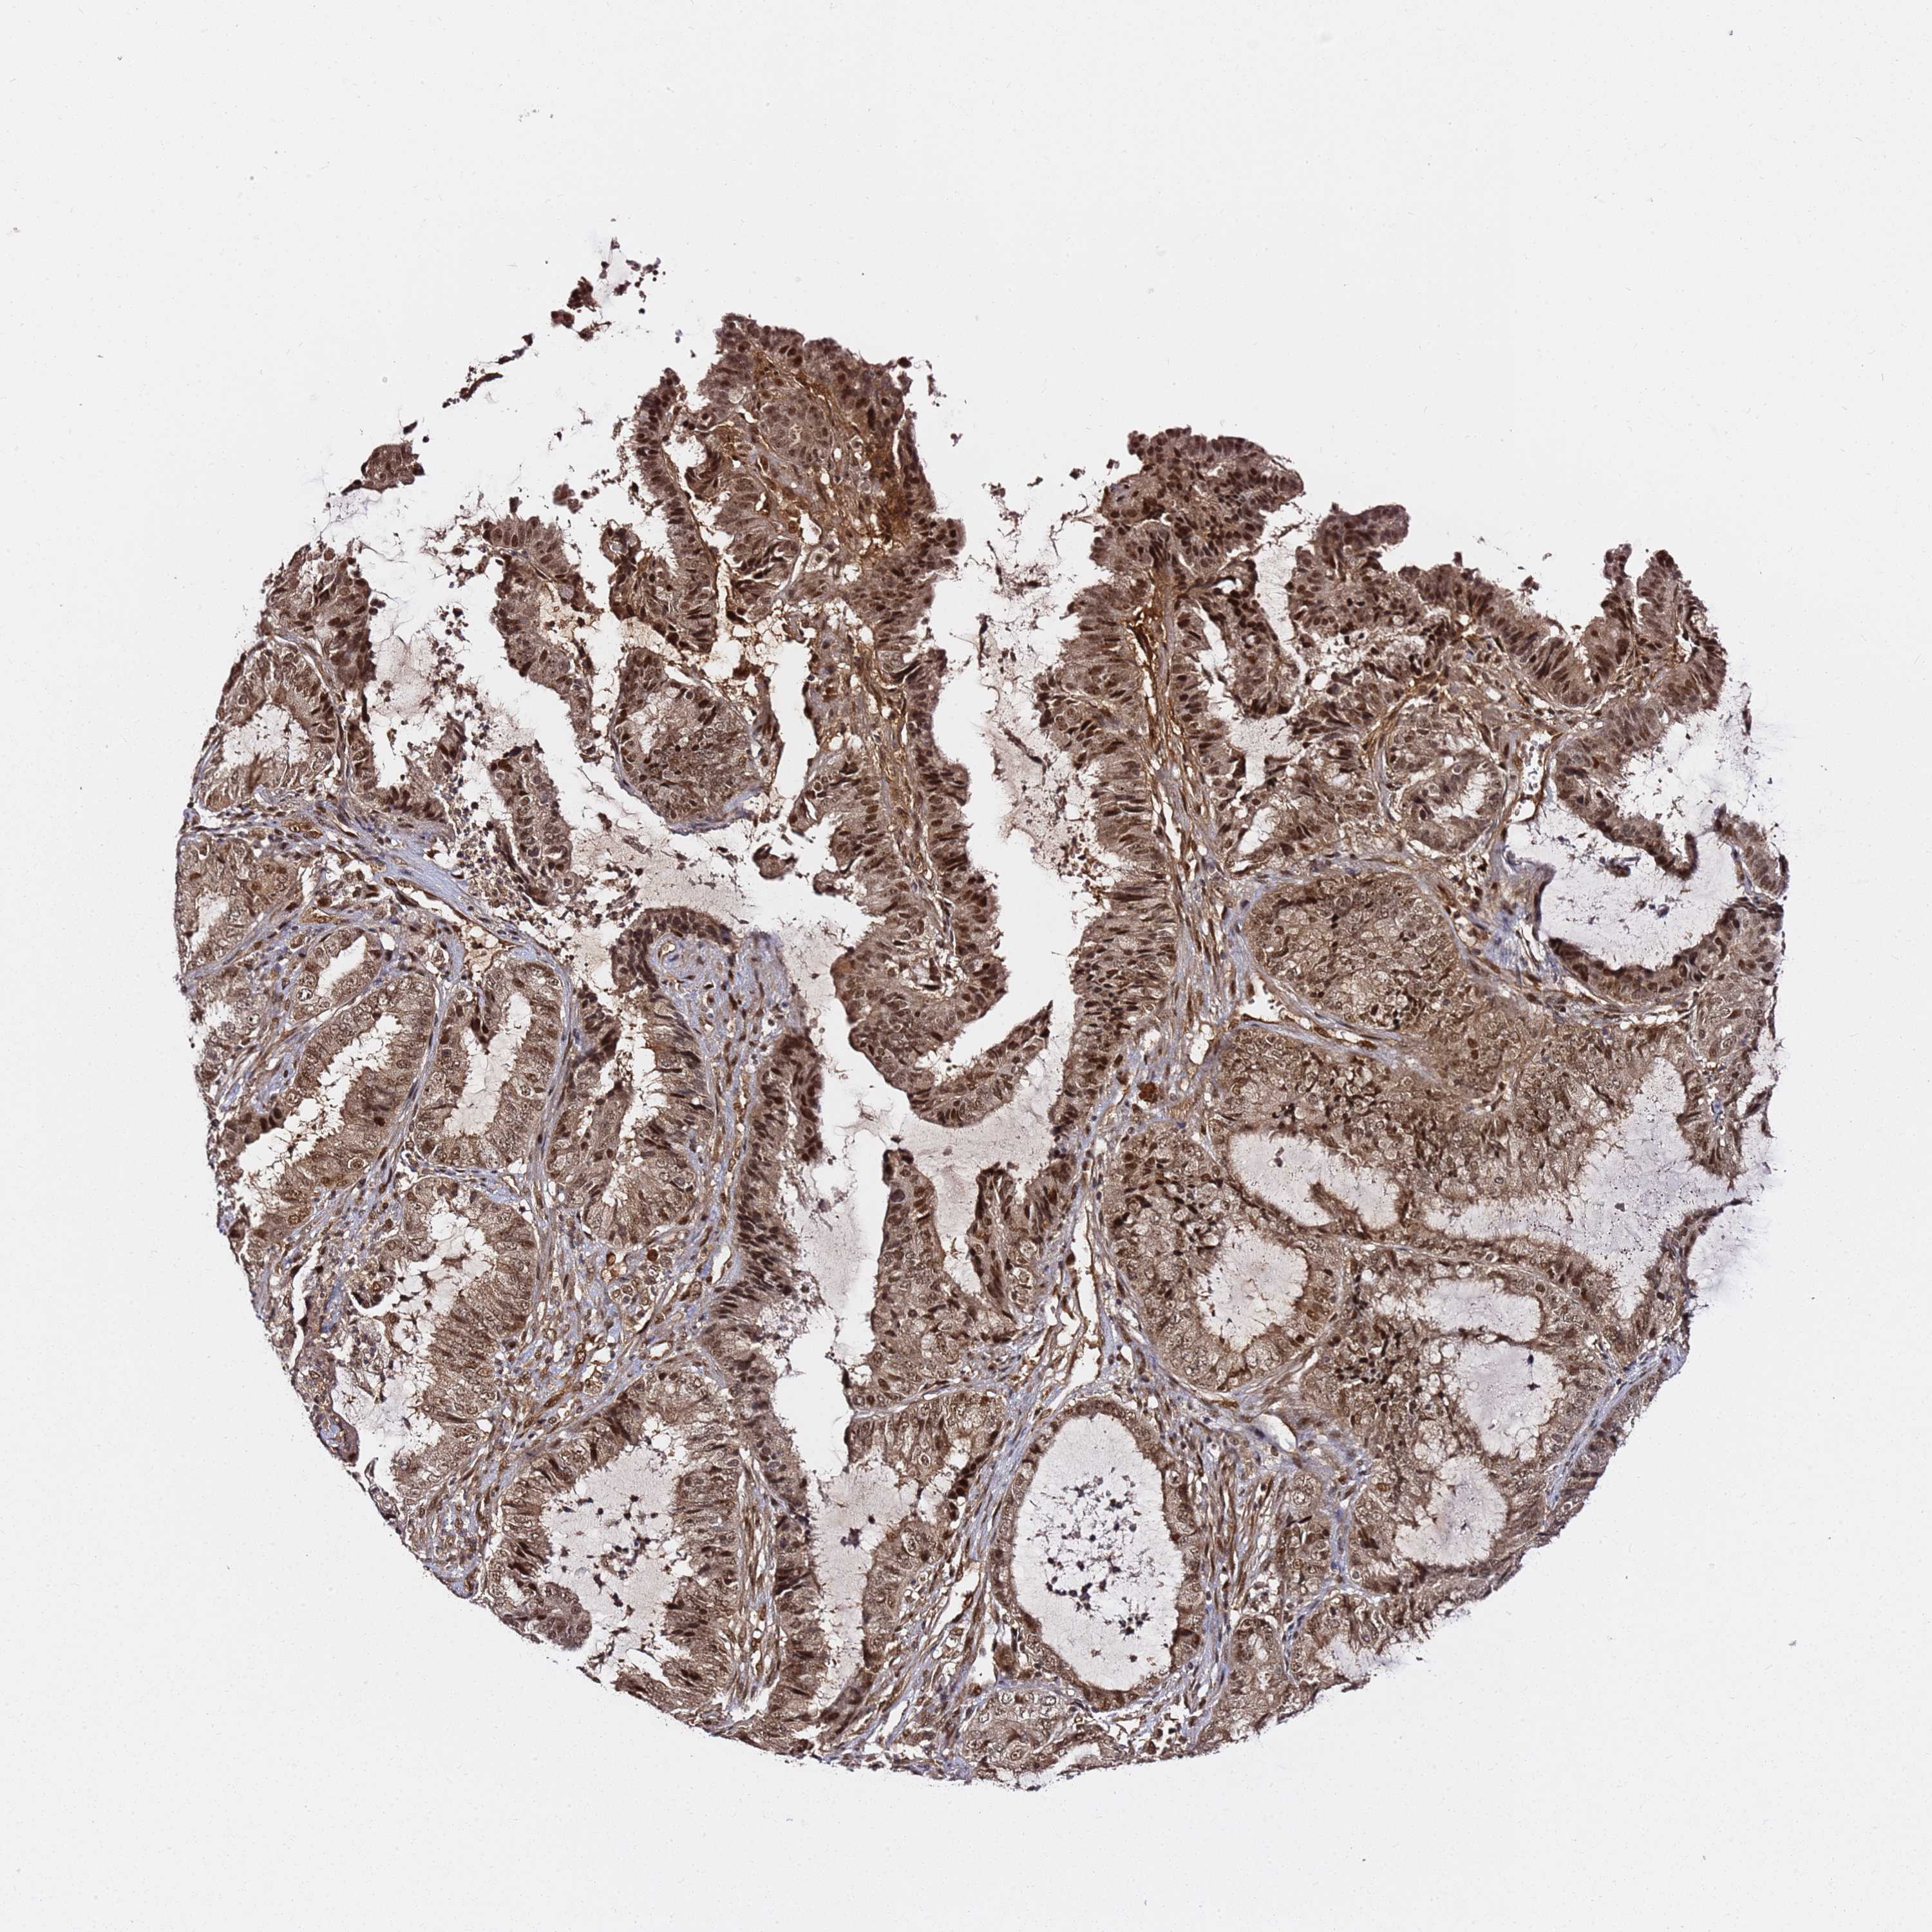

ENDOMETRIAL CANCER - Protein expressioni

A mouse-over function shows sample information and annotation data. Click on an image to view it in a full screen mode. Samples can be filtered based on level of antibody staining by selecting one or several of the following categories: high, medium, low and not detected. The assay and annotation is described here.

Note that samples used for immunohistochemistry by the Human Protein Atlas do not correspond to samples in the TCGA dataset.

Antibody stainingi

Antibody staining in the annotated cell types in the current human tissue is reported as not detected, low, medium, or high, based on conventional immunohistochemistry profiling in selected tissues. This score is based on the combination of the staining intensity and fraction of stained cells.

Each image is clickable and will lead to virtual microscopy that enables deeper exploration of all samples and also displays staining intensity scores, fraction scores and subcellular localization as well as patient and tissue information for each sample.

Antibody HPA045780

Staining

High

Medium

Low

Not detected

Intensity

Strong

Moderate

Weak

Negative

Quantity

>75%

75%-25%

<25%

None

Location

Nuclear

Cytoplasmic/membranous

Cytoplasmic/membranous,nuclear

Adenocarcinoma, NOS